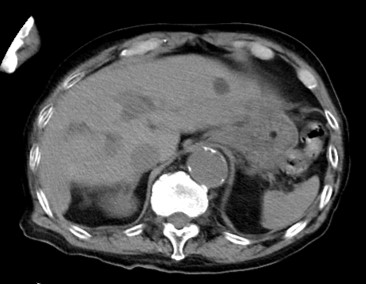

②のmAs不足に対しては、再構成方法のパラメータ調整で調整することも可能である。GEヘルスケア社独自の逐次近似画像構成技術・ASiR-Vは空間分解能を保ちつつ従来比最大91%のノイズ低減が可能である。この技術はmAs不足の場合のノイズリカバリーや低コントラスト分解能向上、被ばく低減などに応用可能である。ASiR-Vではノイズ低減度合いを10-100%で選択可能なので当院ではルーチンでASiR-V30%を使用し、これは1.36倍の線量相当のノイズ低減効果がある。

また、人工骨頭などの高吸収体によるアーチファクトに対しては、Smart MARという金属アーチファクト低減アルゴリズムを適用させることにより補正が可能である。金属インプラントの入っていることの多い高齢患者に対して有効な機能である。

Maxima_hachiojisanno12.jpg

図8 GEヘルスケア社の各種画質向上アルゴリズム使用画像